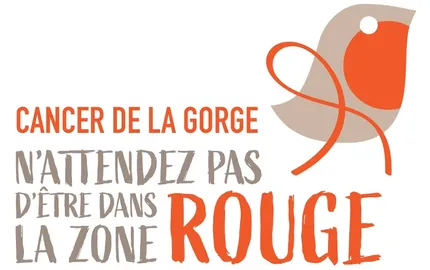

- Cancers ORL

Campagne Rouge Gorge : l’Institut Curie se mobilise contre les cancers de la gorge

27/03/2026